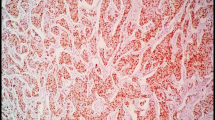

For two-color FISH analysis, 4-μm-thick TMA sections were cut, mounted on positively charged glass slides (Superfrost™ Plus, Thermo Fisher Scientific) and dried. Sections were then deparaffinized in xylene, dehydrated in absolute ethanol, and subsequently pretreated using a commercial kit (Vysis paraffin pretreatment reagent kit, Abbott molecular) whereby the slides were immersed in pretreatment solution for 30 min at 80 °C followed by incubation in protease solution for 37 min at 37 °C.

FISH analyses were performed using a dual-probe kit containing an orange-labeled CCND1-specific and green-labeled CEP 11 centromere probe (Vysis CCND1/CEP 11 FISH probe kit, Abbott molecular). Hybridization and post-hybridization washes were performed according to the manufacturer’s protocol. Slides were briefly dipped in dH2O after being washed and ProLong® Gold Antifade Mountant with DAPI (Thermo Fisher Scientific) was applied directly.

Gene-specific and centromere copy numbers were estimated by counting ≥20 nuclei in two tissue cores per case at 100x magnitude. A ratio of 1.8 or higher for CCND1/CEP was classified as CCND1 amplification. All FISH analyses were performed by one investigator (Embretsén-Varro E.) blinded to all clinical information.